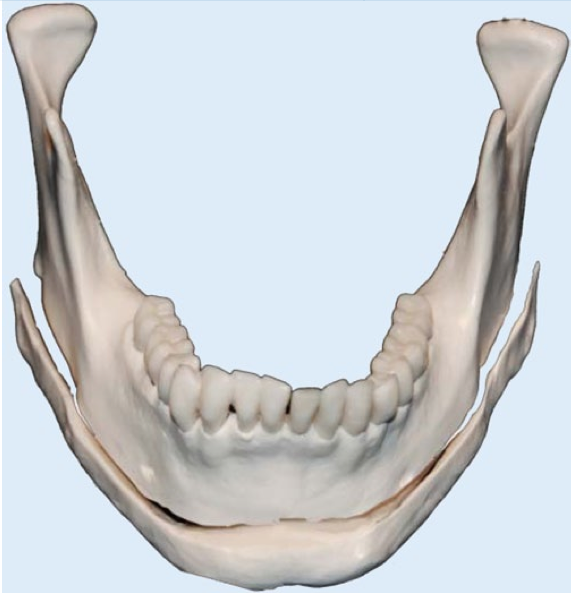

... why not going for a cut like below to fix so-called "inward gonions" ? You can then imagine a variety of movements and segmentations to attain the desired result, akin to chin osteotomy.

... why not going for a cut like below to fix so-called "inward gonions" ? You can then imagine a variety of movements and segmentations to attain the desired result, akin to chin osteotomy.